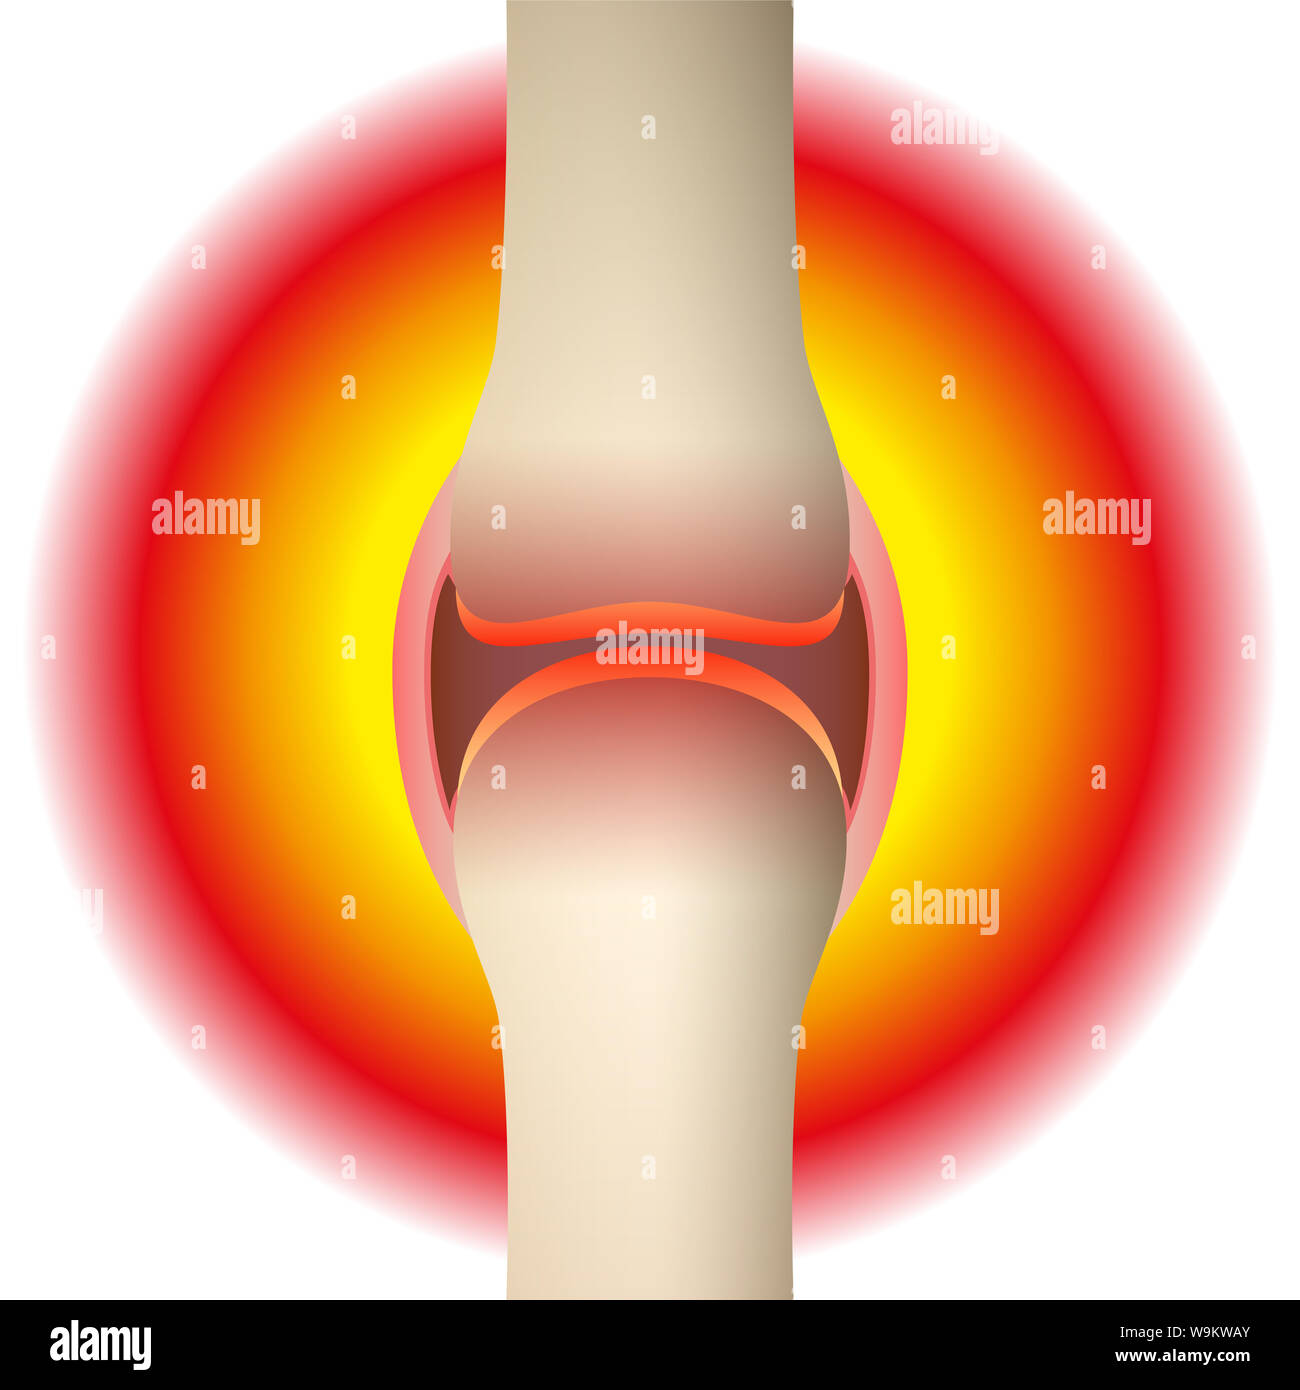

Joint pain - schematic anatomical graphic of a synovial joint with arthritis, rheumatism, gout, osteoarthritis or inflammation. Stock Photohttps://www.alamy.com/image-license-details/?v=1https://www.alamy.com/joint-pain-schematic-anatomical-graphic-of-a-synovial-joint-with-arthritis-rheumatism-gout-osteoarthritis-or-inflammation-image264124419.html

Joint pain - schematic anatomical graphic of a synovial joint with arthritis, rheumatism, gout, osteoarthritis or inflammation. Stock Photohttps://www.alamy.com/image-license-details/?v=1https://www.alamy.com/joint-pain-schematic-anatomical-graphic-of-a-synovial-joint-with-arthritis-rheumatism-gout-osteoarthritis-or-inflammation-image264124419.htmlRFW9KWAY–Joint pain - schematic anatomical graphic of a synovial joint with arthritis, rheumatism, gout, osteoarthritis or inflammation.